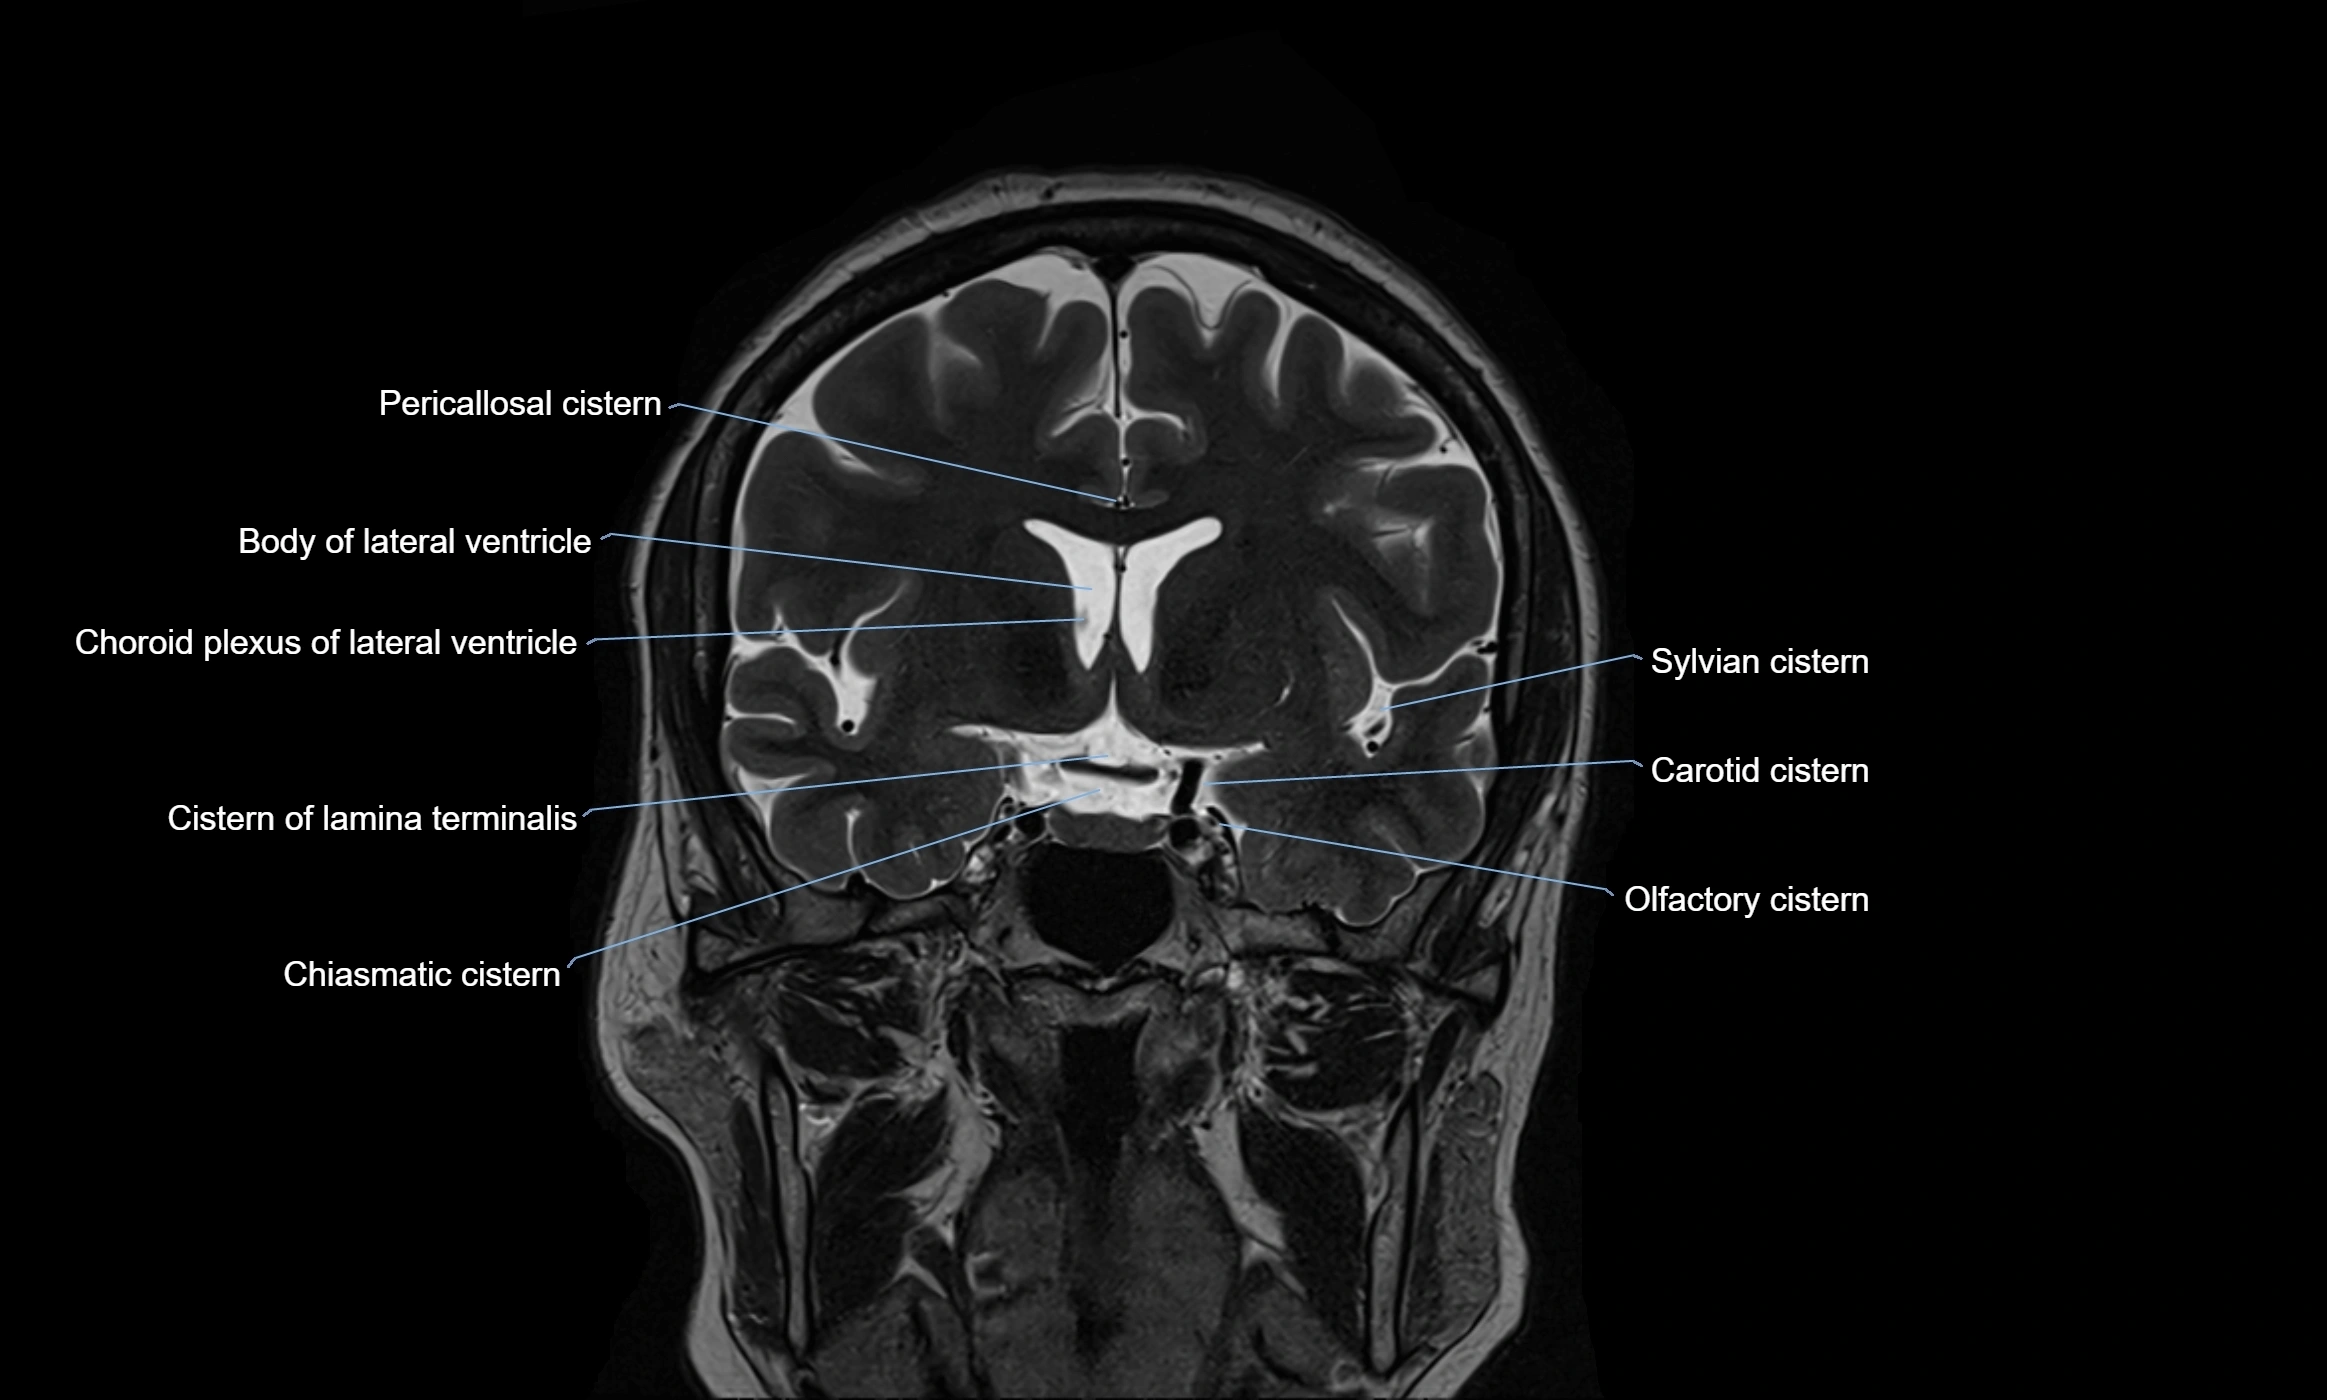

MRI images

image